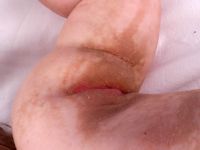

Ichthyosis Histrix van het Curth-Macklin type is een zeldzame vorm van ichthyosis, gekenmerkt door zuiltjes van adherente hyperkeratose en hyperkeratose van de handpalmen en voetzolen. De afwijkingen kunnen over het hele lichaam voorkomen maar zitten vooral op de strekzijde van armen en benen. Het kan ook beperkt zijn tot alleen knieën en ellebogen. Geen blaarvorming. Het is autosomaal dominant erfelijk maar spontane mutaties komen ook voor. In dat geval zit het niet in de familie. Dragers van het gen kunnen weinig of veel afwijkingen hebben. Het betreft een mutatie in het gen voor keratine 1 (KRT1) op chromosoom 12q13.13. Dezelfde mutatie en bijbehorende huidafwijkingen kunnen worden gevonden in lineaire epidermale naevi en epidermale naevus syndromen, tot wel 20% blijkt een mosaïcisme van ichthyosis hystrix.

Ichthyosis hystrix